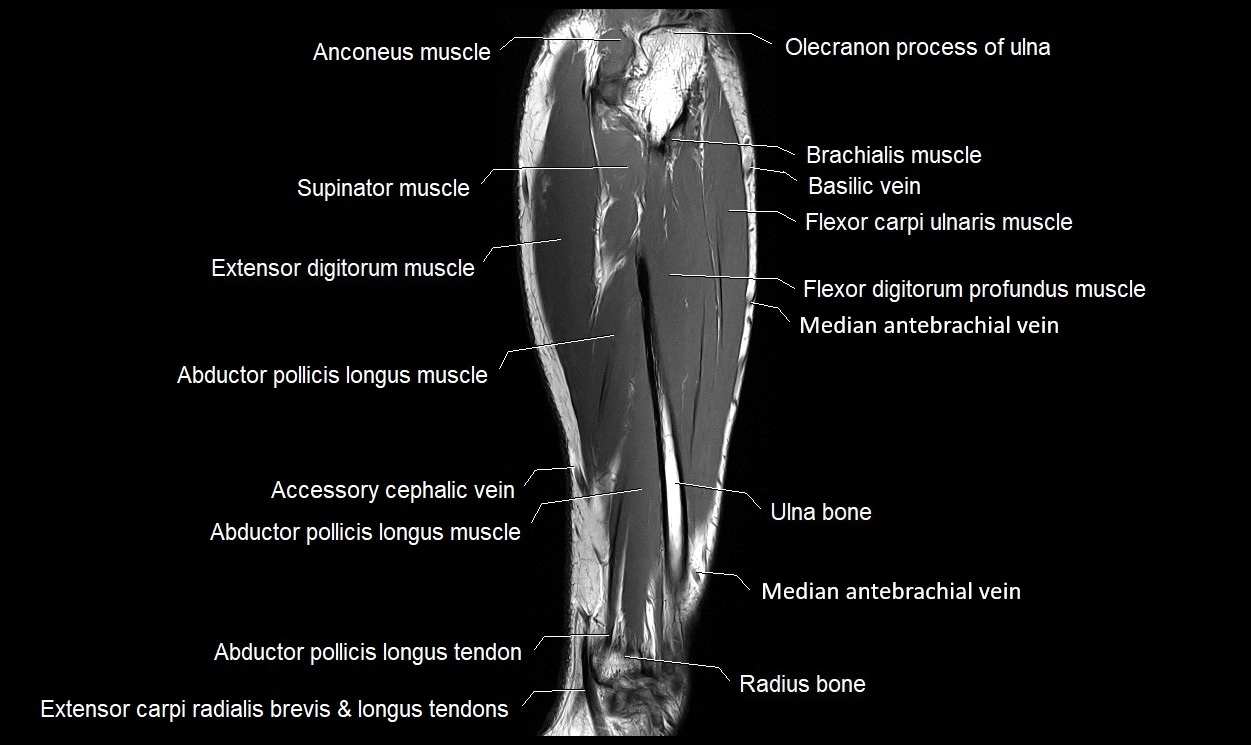

The abductor pollicis longus (APL) tendon is a strong, flat tendon that arises from the abductor pollicis longus muscle in the posterior compartment of the forearm. It is one of the key tendons of the first dorsal compartment of the wrist, alongside the extensor pollicis brevis (EPB) tendon. Its main function is to abduct and extend the thumb at the carpometacarpal (CMC) joint, assisting in grasp and pinch movements.

The APL tendon is highly variable and often has multiple slips, sometimes inserting onto both the base of the first metacarpal and the trapezium. Due to its close anatomical relationship with the EPB tendon within a tight fibro-osseous tunnel, the APL is commonly involved in De Quervain’s tenosynovitis, a painful inflammatory condition of the radial wrist.

Origin, Course, and Insertion

• Origin: Posterior surface of the ulna and radius, and the adjacent interosseous membrane, distal to the supinator muscle

• Course:

• Tendon forms in the distal third of the forearm and passes obliquely downward and laterally.

• Travels beneath the extensor retinaculum within the first dorsal compartment of the wrist.

• Often runs in a common synovial sheath with the extensor pollicis brevis tendon.

• Insertion:

• Main insertion on the lateral base of the first metacarpal bone.

• Accessory slips may insert into the trapezium, thenar fascia, or abductor pollicis brevis tendon.

Relations

• Anteriorly: Radial artery and tendons of the flexor carpi radialis and brachioradialis.

• Posteriorly: Radius and the insertion area of the extensor pollicis longus.

• Laterally: Extensor pollicis brevis tendon (in same compartment).

• Medially: Extensor carpi radialis longus and brevis tendons.

• Superiorly: Extensor retinaculum and subcutaneous tissues of the radial wrist.

MRI Appearance

• T1-weighted images:

• Tendon: Low signal (dark) continuous band extending to the first metacarpal base.

• Muscle belly: Intermediate signal.

• Surrounding fat: Bright, aiding tendon visualization.

• Pathology: Tendon thickening, irregularity, or focal intermediate signal in tendinopathy.

• T2-weighted images:

• Normal tendon: Low signal intensity, darker than on T1.

• Surrounding sheath: Low to intermediate signal.

• Pathology: Bright hyperintense signal in or around tendon in tenosynovitis.

• Fluid in sheath: well-defined bright rim encircling tendon.